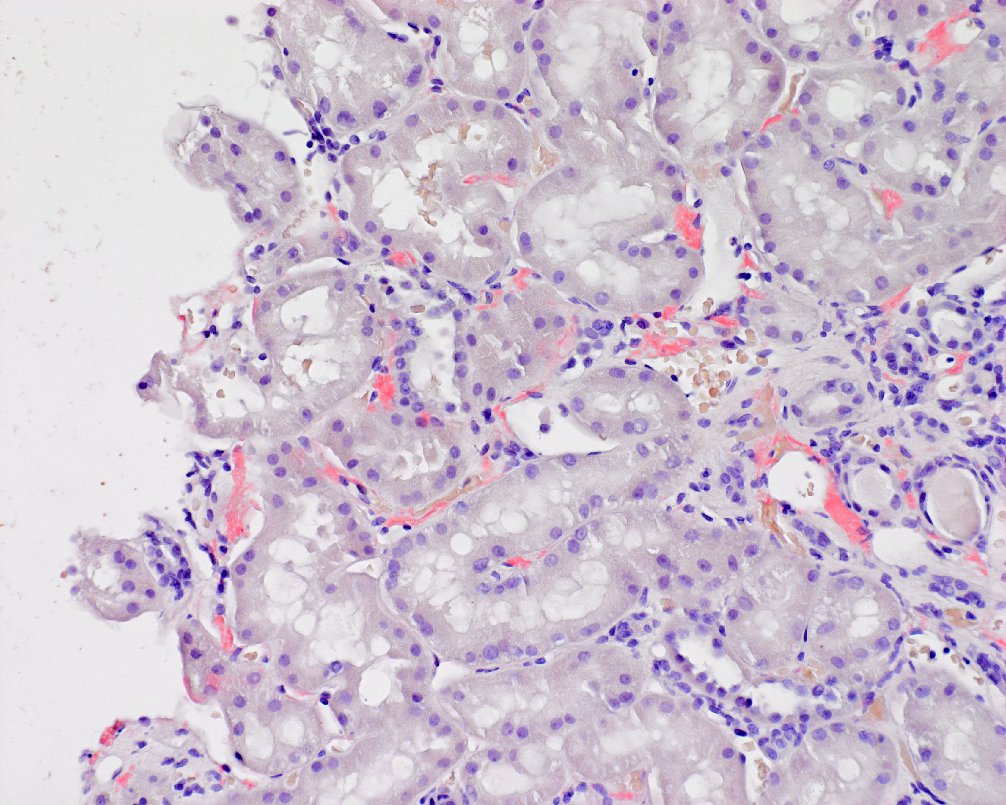

Anti-CD38 #Daratumumab Treatment of #Chronic Active #AntibodyMediated Kidney Allograft #Rejection #VisualAbstract by 💙🦋 Jade Teakell kireports.org/article/S2468-…